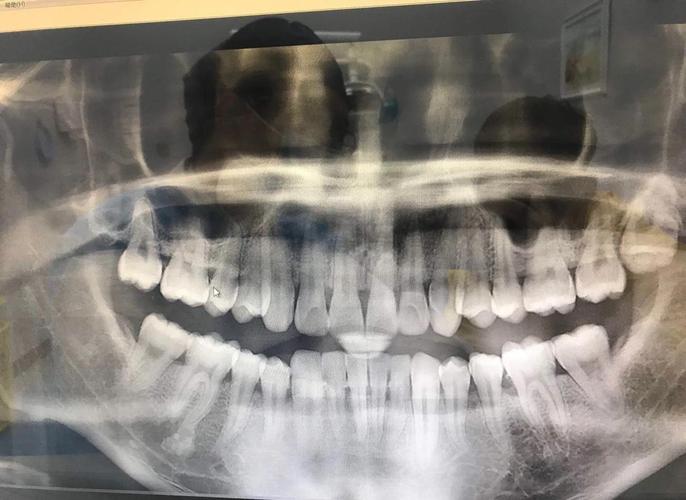

矫正前评估:无论是否计划拔除智齿,矫正前均需拍摄全景片或CBCT,明确智齿的位置、萌出状态、与邻牙及牙根的关系,若存在阻生、倾斜或潜在病变(如囊肿、牙根吸收),建议在矫正前拔除,避免矫正中因智齿引发感染、牙齿移动受阻或矫正后复发。